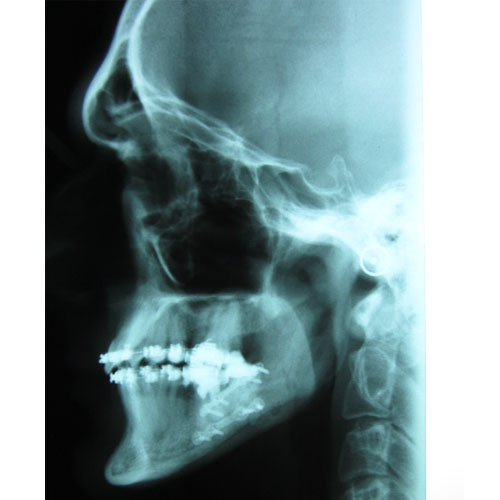

Leczenie ortodontyczne może być rozpoczęte w każdym wieku. Niektóre wady wymagają jednak leczenia kompleksowego, wielospecjalistycznego. Skojarzone leczenie dotyczy wad ortognatycznych, czyli wynikających z nieproporcjonalnej budowy szkieletu. Przykładem takiego leczenia jest leczenie progenii.

Nasze rezultaty